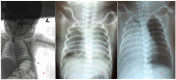

In this case report, we described a rare complication-lung torsion after esophageal atresia repair in a newborn. Torsion of the lung is a critical condition in which either the entire lung or a lung lobe twists, leading to occlusion of blood vessels and airways. The patient's clinical condition was poor after the primary operation. An emergency thoracotomy showed 180° torsion of the right upper lobe (RUL) and right middle lobe (RML). After detorsion, perioperatively, the lung was gradually reperfused and had a normal appearance. After surgery, the patient was unstable, which culminated in a fatal end (bradycardia, reperfusion injury). Immediate intervention can preserve the affected lung or lung lobe. However, pulmonary torsion typically has a poor prognosis due to misdiagnosis and delayed treatment. Additionally, diagnosis in the neonatal period is even more challenging because the clinical symptoms are nonspecific. In any case, the question is whether detorsion is the right solution or whether a segmentectomy is necessary.